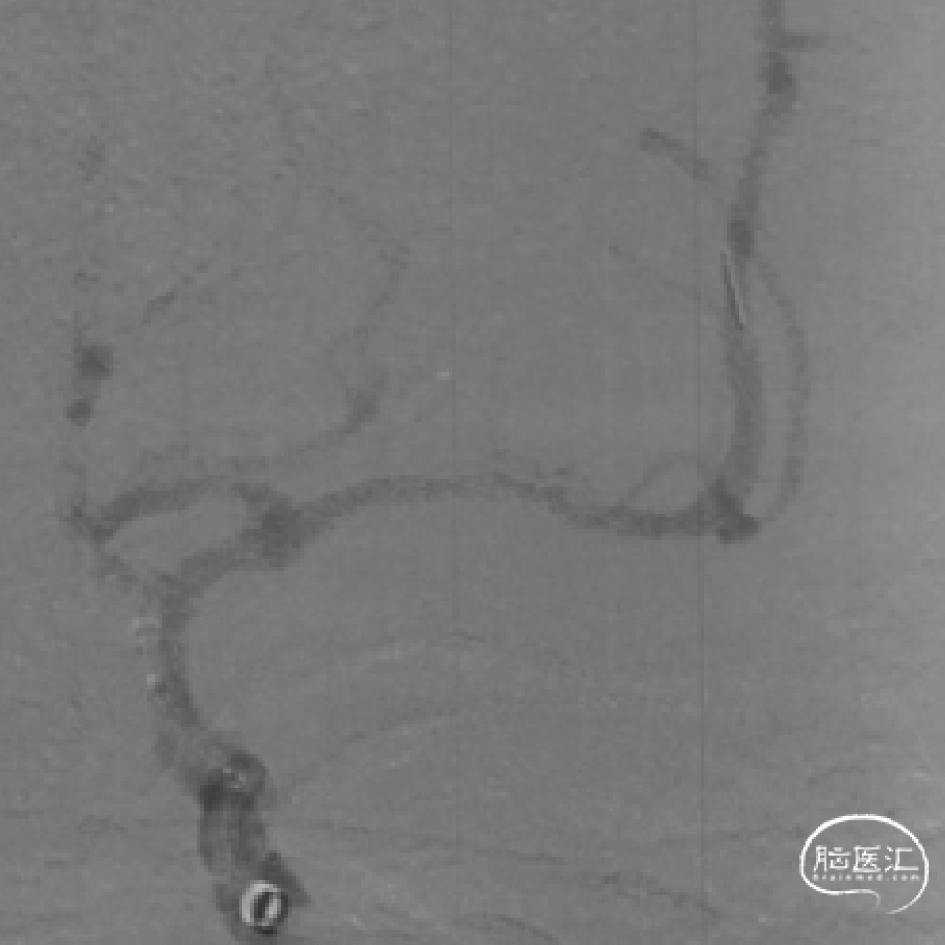

术中造影

微导管到位,造影确认真腔

释放Syphonet® 5/35取栓支架

第一次抽拉取栓后血管再通,M1段重度狭窄,颞支开口血栓影

使用Fastunnel® 2/15在M1段狭窄处进行扩张

扩张后将Fastunnel®输送至M2段以远

通过Fastunnel®释放Syphonet®取栓支架,覆盖颞支血栓

第二次抽拉取栓后取出白色血栓,颞支复现,狭窄处仍有夹层样改变

再次将Fastunnel®输送至M2段

通过Fastunnel®释放Enterprise 2 4/23mm支架覆盖狭窄段并再次使用Fastunnel®扩张

术后即刻支架内血流通畅,无残余狭窄

术后即刻eTICI3级再通